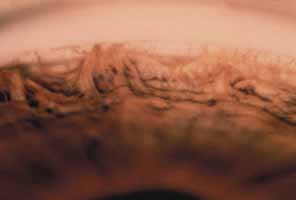

There are no anomalies of the iris or cornea, although stretching effects secondary to elevated intraocular pressure may be seen. This trabecular maldevelopment presents in two forms. In the more common form, the iris inserts flatly into the trabecular meshwork at or anterior to the scleral spur (Fig. 1). This insertion usually obscures the ciliary body, although portions of the anterior ciliary body may be seen through a thickened trabecular meshwork if the angle is viewed obliquely. The level of iris insertion may vary along the angle circumference with portions of iris inserting behind the scleral spur and other portions inserting anterior to it. The surface of the trabecular meshwork may have a stippled, orange-peel appearance, and the peripheral iris stroma may appear thinned because of stretching from enlargement of the eye.

Fig. 1 Flat anterior iris insertion in trabeculodysgenesis. The iris inserts flatly and abruptly into the trabecular meshwork. Small iris processes are often visible on the trabecular surface. (Hoskins HD Jr., Shaffer RN, Hetherington J: Anatomical classification of the development of glaucomas. Arch Ophthalmol 102:1331, 1984. Copyright © 1984, American Medical Association.)